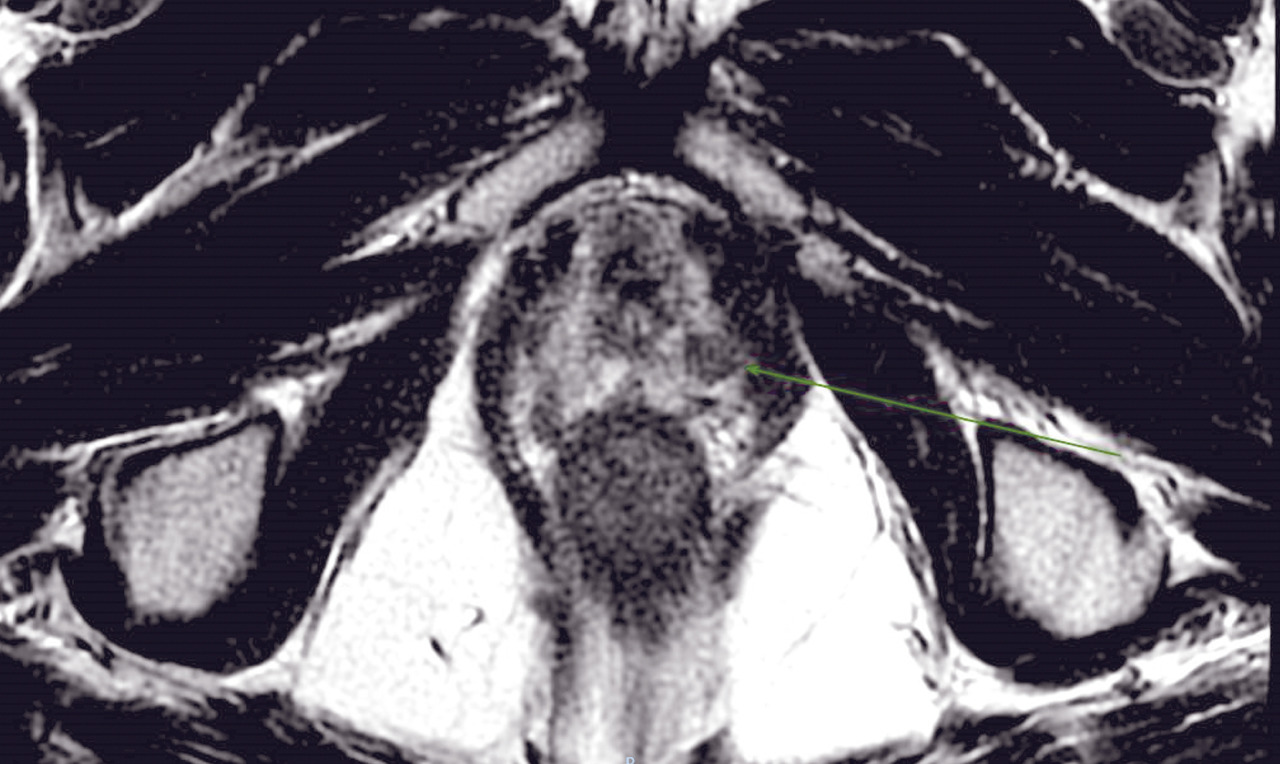

L’IRM multiparamétrique (IRM-mp) de la prostate joue un rôle fondamental dans la détection du cancer de la prostate : le protocole multiparamétrique, qui prévoit des séquences anatomiques en T2, T1 en perfusion (dynamic contrast-enhanced magnetic resonance imaging, DCE-MRI) et en diffusion (diffusion weighted imaging, DWI), est en mesure de fournir une combinaison d’informations anatomiques, biologiques et fonctionnelles nécessaires pour une définition plus précise des lésions suspectes (fig. 1 et 2).

À ce jour, avec la diffusion d’outils de plus en plus sophistiqués et précis pour effectuer des biopsies avec fusion d’images entre l’IRM multiparamétrique et l’échographie transrectale en temps réel, la biopsie avec connaissance de l’anatomie prostatique sur la base des images d’IRM réalisée sous guidage échographique est devenue une approche indispensable, permettant de faire évoluer les biopsies systématisées, réalisées « à l’aveugle», vers des biopsies ciblées. De nombreuses études ont montré que l’échantillonnage ciblé, en plus de l’approche systématique, est mieux corrélé au score de Gleason pathologique, tandis que d’autres ont montré une meilleure performance en termes de sensibilité et de spécificité de la biopsie ciblée par rapport à la réalisation des biopsies avec approche systématique, réduisant de manière significative le taux de détection des tumeurs cliniquement non significatives. Par conséquent, la réalisation de l’IRM avant de programmer les biopsies est de plus en plus recommandée afin de :

Les études menées pour l'évaluation des performances diag­nostiques du protocole multiparamétrique ont montré une sensibilité et une spécificité élevées, avec une valeur prédictive négative entre 63 % et 91 % pour les cancers de la prostate de tout grade et entre 92 et 100 % pour les tumeurs cliniquement plus significatives (score de Gleason > 6). L’IRM doit toujours être effectuée avec tous les détails concernant les valeurs de PSA (récentes et anciennes si disponibles), le toucher rectal, l’âge du patient, les comorbidités et les antécédents familiaux. L’ensemble de ces éléments peut être décisif dans la sélection des patients candidats à la biopsie, avec deux avantages assurés plus spécifiquement par l’IRM : d’une part, de réduire les biopsies inutiles d’environ 25 % et, par conséquent, de prévenir le surdiagnostic et le traitement excessif des tumeurs cliniquement indolentes, non significatives ; d’autre part, d’augmenter le taux de diagnostic de tumeurs cliniquement significatives d’environ 18 %, tumeurs qui autrement ne seraient pas diagnostiquées par les biopsies systématisées, « à l’aveugle ».

Contrairement à la tomodensitométrie (TDM), la résolution spatiale de l’image garantie par l’IRM permet d’élucider l’anatomie zonale de la glande prostatique et de distinguer la portion périphérique de la glande et le tissu néoplasique, qui a un signal intrinsèque différent. De plus, pour les mêmes raisons, l’IRM est en mesure de mieux représenter toutes les structures pelviennes restantes, avec une clarification remarquable de leurs rapports (vessie, rectum, muscles, structures squelettiques, vaisseaux). Ces caractéristiques rendent désormais l’utilisation de l’IRM multiparamétrique également essentielle à des fins de planification thérapeutique (bilan d’extension locorégional avant traitement local, par exemple de chirurgie ou de radiothérapie externe).